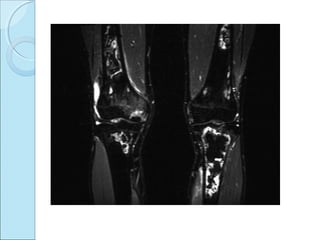

 MRI FINDINGS

vitality of underlying bone

integrity of overlying cartilage.

T1W & STIR---coronal & sagittal.unstable.

Stable –adjacent edema

Stable OCD –coronal & sagittal T2W shows lesion of

medial condyle and marrow edema .

Coronal T2W unstable OCD with fluid at base of

lesion